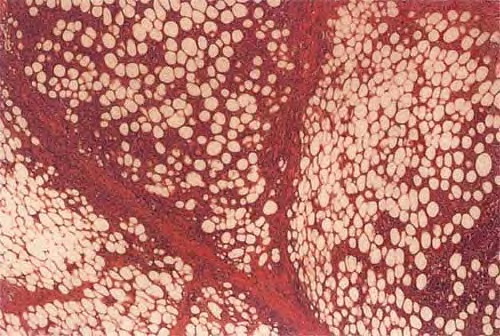

Subcutaneous T-cell lymphoma = اللمفوما التائية الخلايا تحت الجلد